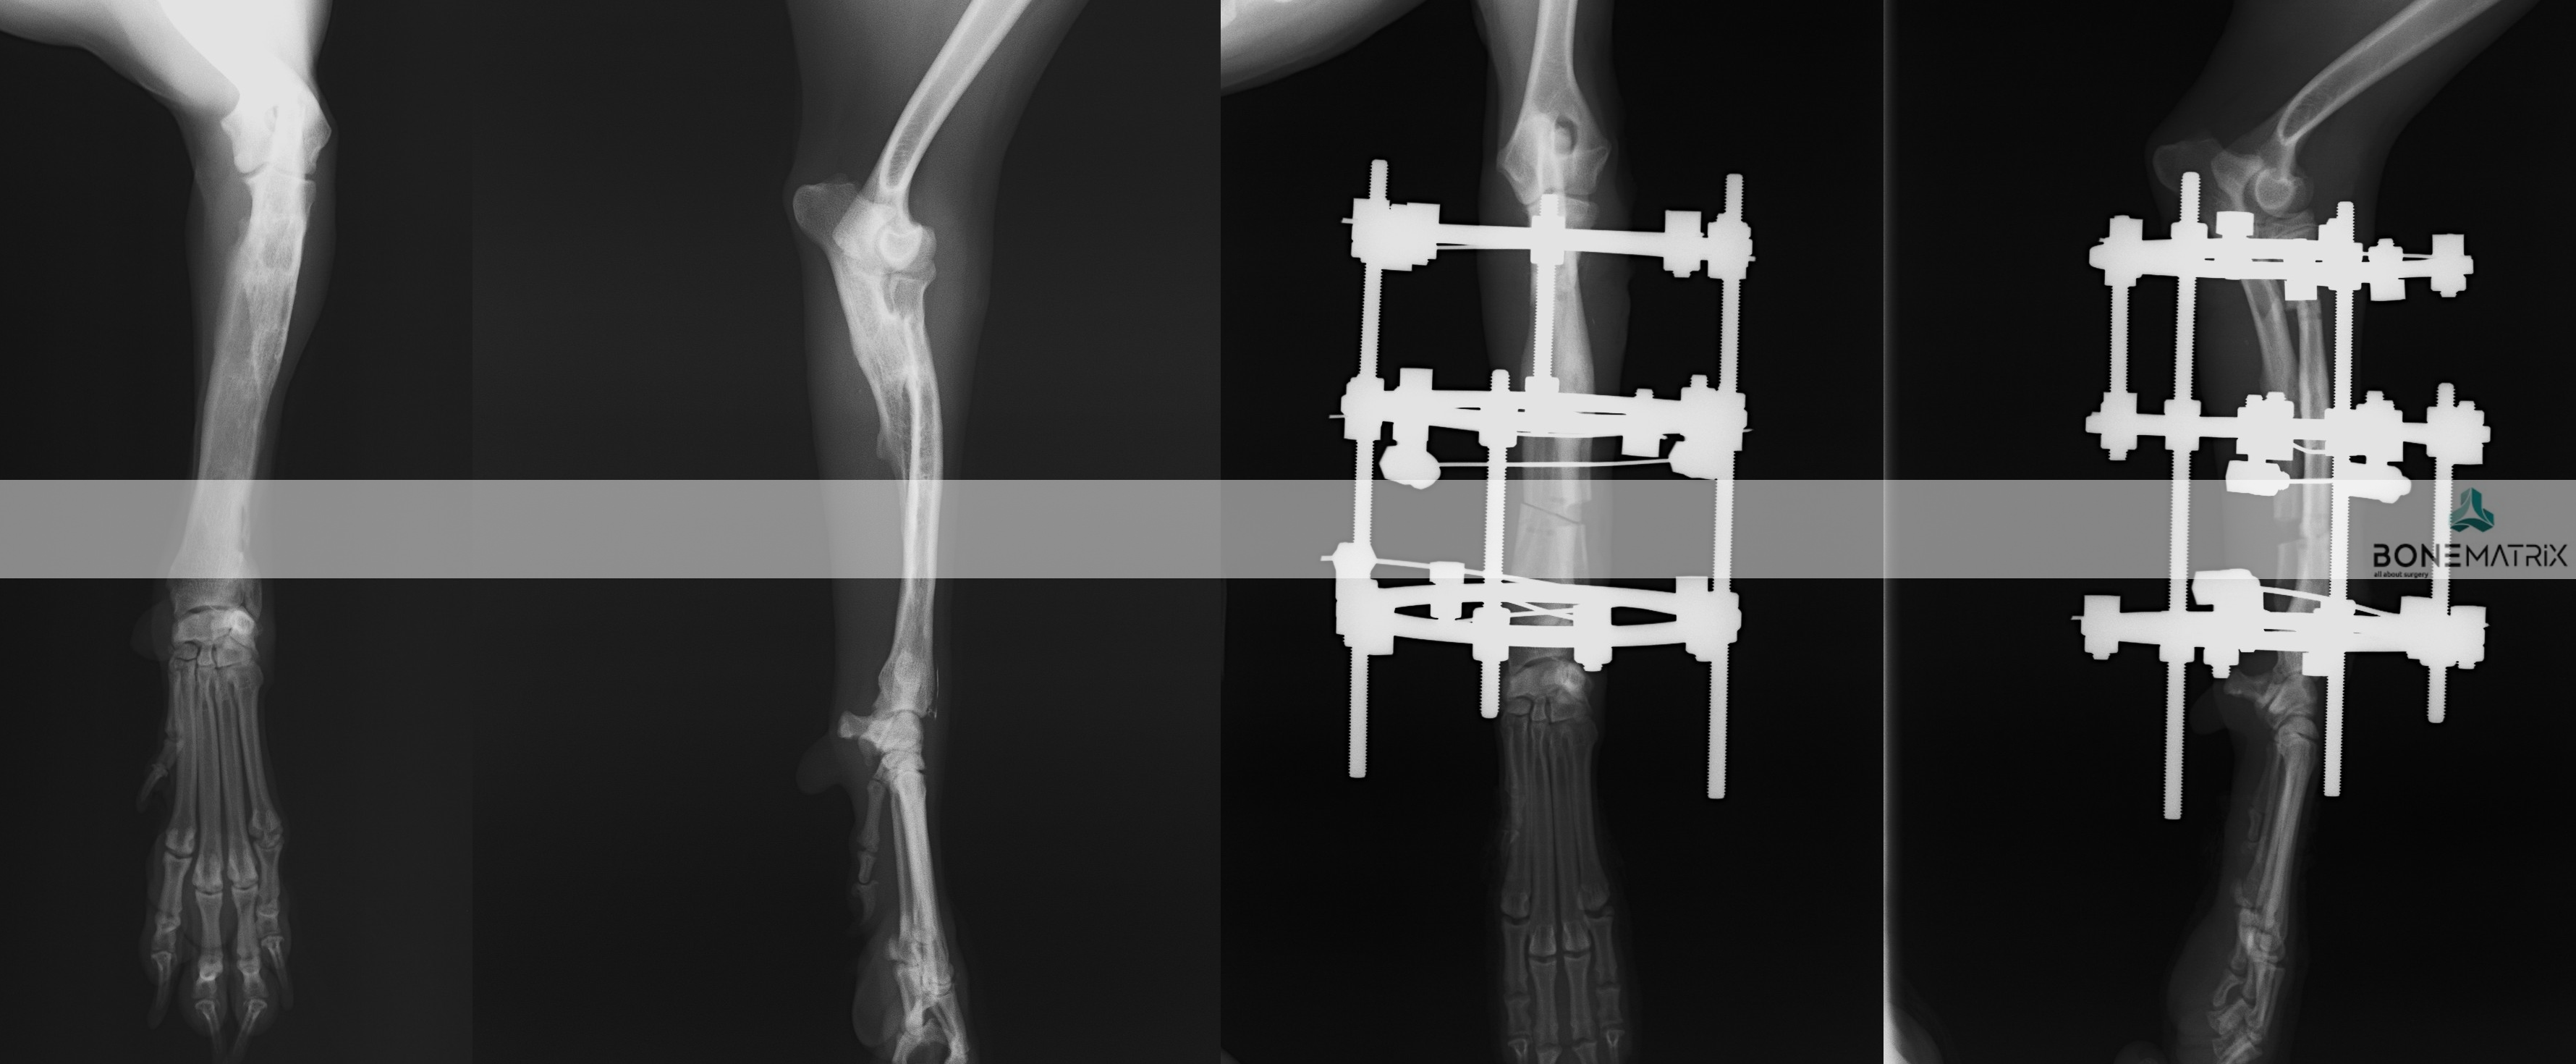

O que é?

Os fixadores externos circulares e semi-circulares consistem num método de estabilização de fraturas que por norma evita que seja realizada uma exposição aberta do foco de fratura. Esta técnica só é utilizada em casos de fraturas muito específicos. É mais frequente a sua utilização como método de correção de deformidades angulares.

Esta técnica consiste num método de estabilização externo ao corpo do animal. São utilizadas para a sua aplicação: K-wires, barras e anéis com diferentes formas.

A utilização desta técnica envolve um nível avançado ou mestre de conhecimento cirúrgico de ortopedia e traumatologia (consoante o objetivo da sua utilização).

Quando é aplicada esta técnica cirúrgica?

Esta técnica cirúrgica pode ser empregue em vários casos, podendo ser incluídas neste grupo:

Qual a taxa de sucesso esperada?

O sucesso da aplicação desta técnica cirúrgica está relacionada com a complexidade da resolução pretendida.

Que complicações podem surgir?